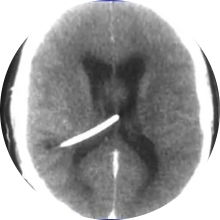

Se realiza un TAC craneal y se observa, una severa hidrocefalia biventricular, secundaria a un voluminoso proceso...